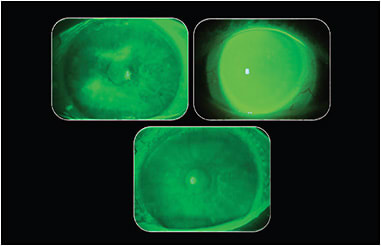

This was demonstrated in two case series performed by Dr. Sheila Morrison at Pacific University. In the first case series, a scleral lens was placed on the right eye of three patients, using fluorescein dissolved into preservative-free (PF) saline as the application solution. Patients wore the lens for eight hours; it was photographed at 30 minutes and at one, two, four, six, and eight hours. Anterior segment optical coherence tomography (AS-OCT) was performed at each time point to monitor lens settling. The average amount of lens settling in the three patients over the eight hours was 133µm. There was little or no fluorescein exchange throughout the eight-hour period (Figure 3).

In the second case series, scleral lenses filled with clear PF saline were placed onto one eye of three patients and photographed with white and cobalt blue light. Following 30 minutes, PF fluorescein drops were instilled onto the superior bulbar conjunctiva every 20 minutes for eight hours (23 drops total). At eight hours, the amount of fluorescein beneath the lens was photographed and compared to the baseline images. OCT was performed at baseline and at eight hours to monitor lens settling. The average amount of settling in the three patients over eight hours was 123µm. The cobalt blue images showed no fluorescein under the lens following eight hours of wear.